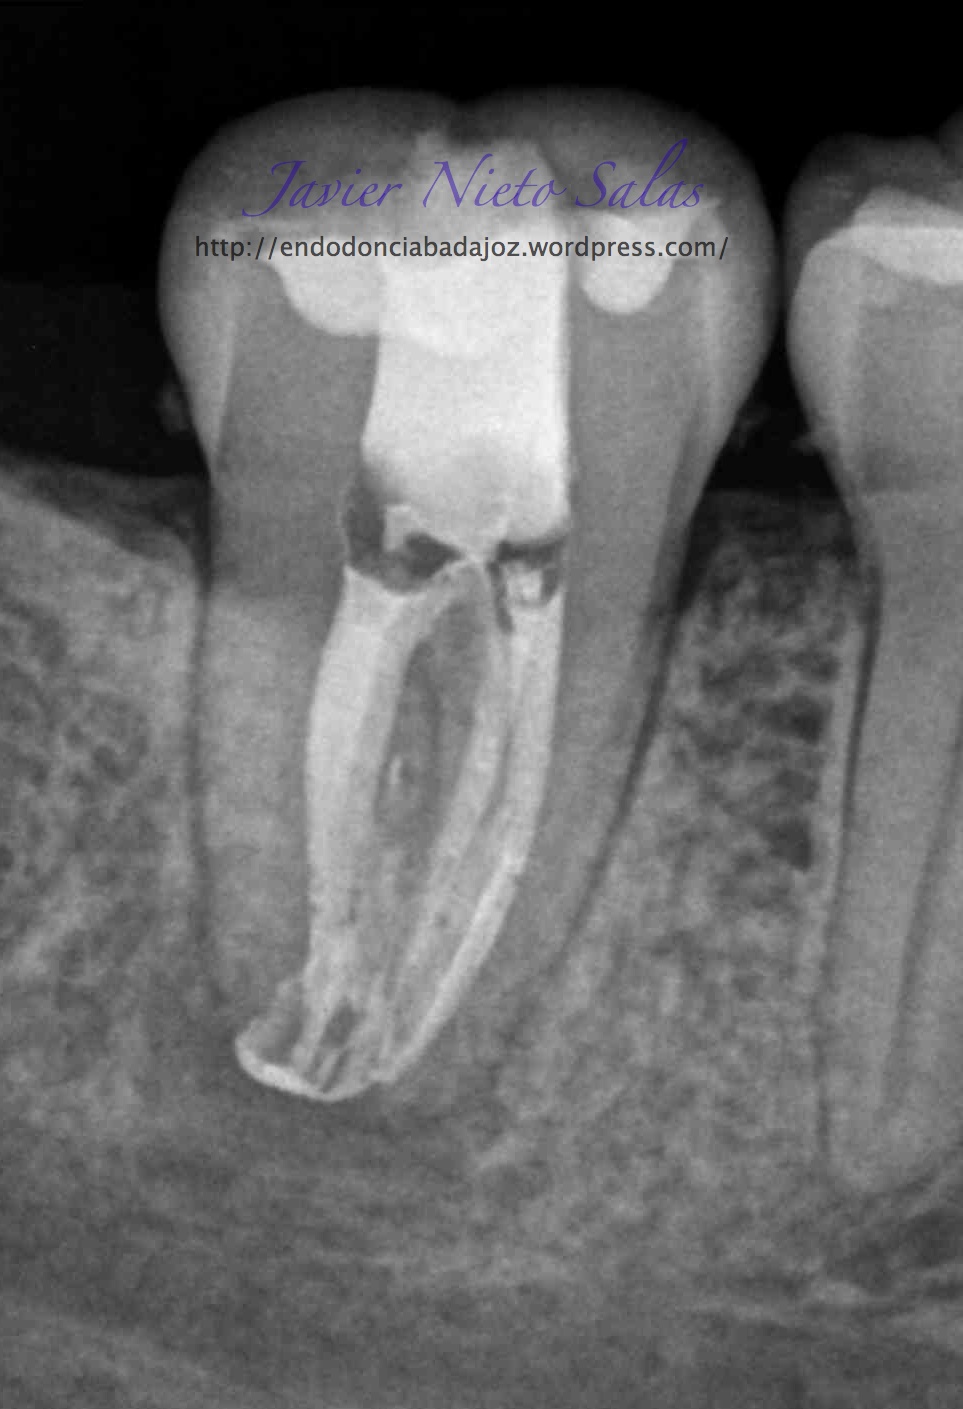

Empezaremos con el primer caso, un 4.7, se trata de una necrosis con afectación periapical.Ante las pruebas diagnósticas, nos fijamos en una fístula muy coronal, un sondaje vestibular puntual, esto nos hace pensar en un diagnóstico diferencial con un Sindrome de Diente fisurado. Sin aparente linea de fisura coronal, no vemos, con la ayuda de la magnificación, linea de fisura, lo que no nos descarta definitivamente que se trate de este síndrome de fisura, pues como ya sabemos pueden aparecer en diferentes tramos de la pieza, clasificando así los diferentes tipos.

Realizamos el tratatamiento de conductos con la sospecha del causante de la necrosis es una fractura vertical, pero no hemos podido ver la linea de fisura.

Se trataría de una cámara pulpar Tipo Ic según la clasificación por el método de Min:

El sistema de Obturación sería con condensación vertical.

(disto)                                                                     (mesio)